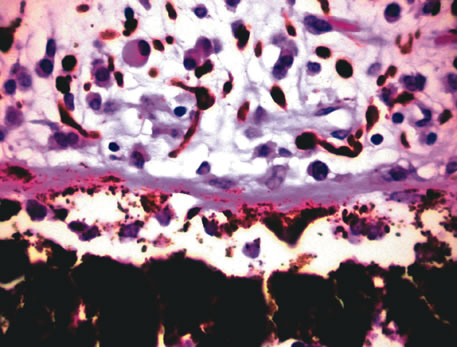

Infectious endophthalmitis refers to inflammation due to an infectious organism, usually bacterial, but it may also be caused by yeast or filamentous fungi. The vitreous is typically involved and supports the growth of the infectious intraocular organism. The reaction to the organism is usually severe and is characterized by abundant polymorphonuclear leukocyte infiltration. The infection is usually accompanied by tissue destruction due to the release of proteolytic enzymes in the severe inflammatory reaction. Uveal and retinal necrosis may occur during these infections. Endogenous endophthalmitis refers to hematogenous dissemination of organisms to the eye and can be seen in cases of septicemia from bacterial or fungal causes. The latter can be caused by Candida or Aspergillus species. Aspergillosis usually causes destructive choroidal inflammation (Fig. 24) with vascular occlusions. The infective organisms are found in the choriocapillaris or along the sub-RPE and sub-retinal space.126

Fig. 24. Aspergillus chorioretinitis. A. Hemorrhagic necrotizing retinitis and choroiditis are noted in a patient with disseminated aspergillosis (hemotoxylin-eosin ×60). B. Note the branching hypae of the organisms involving the retina and choroid (periodic acid–Schiff ×240).